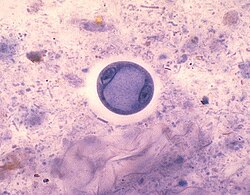

Pełzak okrężnicy (Entamoeba coli) – gatunek pełzaka należącego do typu Amoebozoa. Jest komensalem przewodu pokarmowego człowieka[2]. Występuje w jelicie grubym (intestinum crassum)[3]. Czasami zarażać mogą się psy i inne zwierzęta[4].

Cysty są wielkości 15 – 30 μm i posiadają od 1 do 8 jąder[4]. Według innych[5] posiadają 8 jąder, czasami 16 lub więcej.